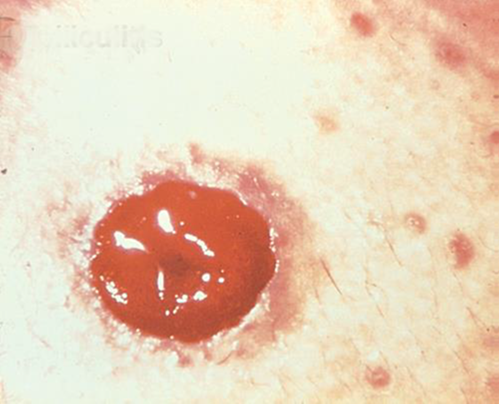

농피증 괴저(Pyoderma Gangrenosum)

설명/원인:

크론병이나 궤양성 대장염과 같은 염증성 장 질환(IBD) 환자에서 흔히 볼 수 있는 염증성 피부 질환.

조짐:

- 불규칙한 모양, 붉은색, 통증, 감염된 궤양, 빨간색에서 보라색으로 말린 가장자리; 다리, 엉덩이, 얼굴, 장루 주위 부위에 나타납니다.